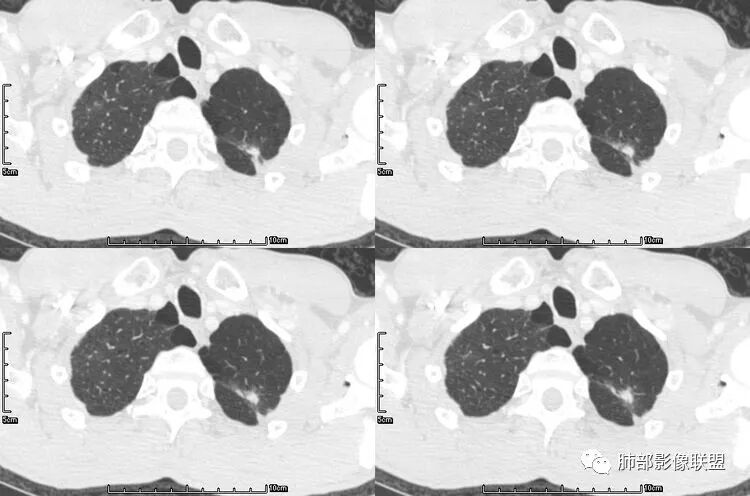

老年男性,咳嗽,咳痰带血2月,左下肺可见一团块影,深分叶,胸膜牵拉,可见坏死,坏死边界清,考虑恶性,双肺多发散在结节影,可见分叶,空洞,胸膜牵拉,考虑转移瘤;

患者老年男性,咳嗽、咳痰、痰中带血伴胸闷2月余。长期大量吸烟史。查肝肾功能、血糖、血脂、心肌酶、电解质、血沉、C反应蛋白、抗“O”、类风湿因子、抗核抗体谱无明显异常。肿瘤标志物提示NSE、CYFRA21-1稍升高。胸部CT:肺气肿背景,左肺下叶后基底段不规则肿块影,见支气管截断,内见大片状低密度区及部分血管影,增强轻度强化,远端空洞形成。双肺多发不规则实性结节影、见毛刺、胸膜牵拉及血管集束,结节内见空洞形成,部分可见血管影,多位于胸膜下。双肺见多发肺大泡。综合考虑左下肺恶性病变并双肺转移。鳞癌或淋巴瘤可能。鉴别血管炎性病变及真菌感染。

张延军:双肺多发结节,空洞影,后者洞壁厚薄不均匀,部分腔内丝丝落落,呈分叶征,边缘见毛刺影,病灶大部分位于胸膜下,与血管相连,右肺下叶前基底段结节近段支气管截断,远端见空腔。左肺下叶病灶密度不均,背段支气管壁增厚,管腔狭窄。考虑1.双肺下叶占位性病变伴肺内空洞性转移 2.多原发的占位 3.肉芽肿性血管炎代排。

背景是慢阻肺背景。病灶是多发结节伴空洞,内部见结节影,即空洞内结节,符合得有:GPA,癌,结核,真菌(隐球菌,曲霉)

脐凹征、粗短毛刺、深分叶、中央结构杂乱

本病例左肺下叶肿块,有深分叶、毛刺、胸膜牵拉凹陷、支气管截断及纵隔内淋巴结肿大等征象,都均支持病灶为恶性,如腺癌,而且叶间裂的多发结节也提示是腺癌来源可能大;双肺多发结节、肿块,大部分病灶有分叶、毛刺及胸膜凹陷的恶性征象,与原发肿瘤本身的性质有关,所以应该与左肺下叶肿块同源,而且双肺多发病灶内空洞也具有多样性;